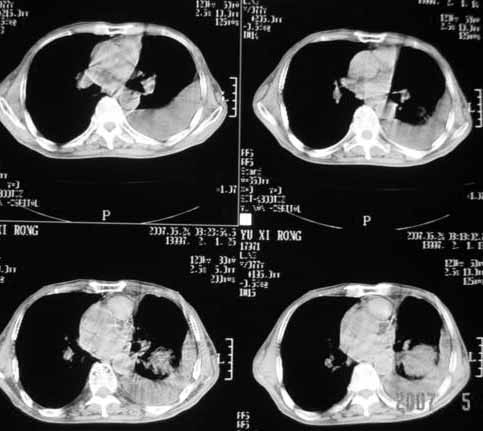

以下是引用luochengyi在2007-5-24 14:33:00的发言:[br]考虑左下肺癌。左侧胸腔积液。

以下是引用adams在2007-5-24 17:12:00的发言:[br]支持“考虑左下肺癌,左侧胸腔积液,建议胸水检查”。[br] [br]

以下是引用fumaogui在2007-5-24 16:20:00的发言:[br]左侧胸腔积液.[br]左下叶不张考虑中心型肺癌[br]建议纤支镜检查.